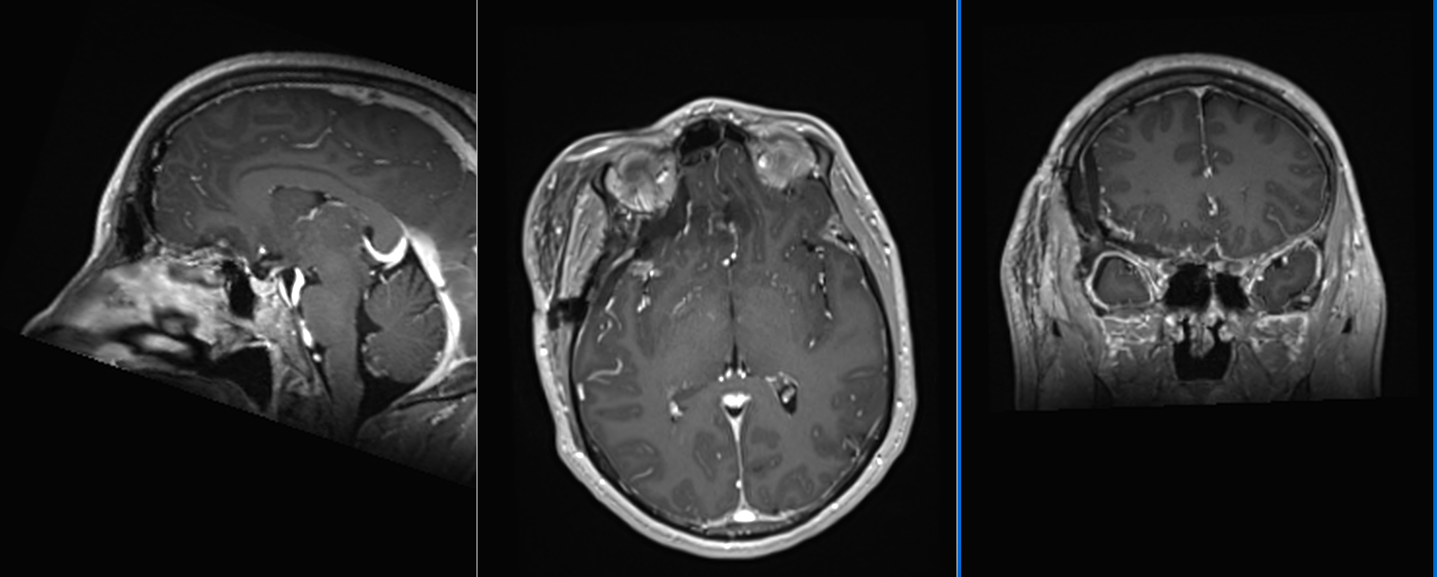

RMN cerebral de control efectuat a doua zi după operație confirmă rezecția completă a tumorii și absența oricăror complicații.